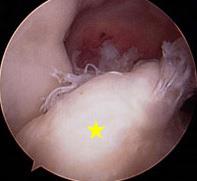

Figura artroscópica de ligamento cruzado anterior roto [estrella amarilla]

• Reconstruir un ligamento cruzado anterior roto